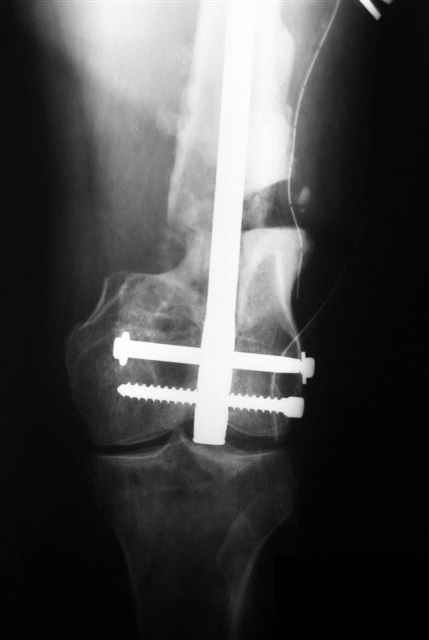

Произвели операцию на левом бедре. Остеотомия параоссальной мозоли, репозиция отломков "конец в конец", с хорошим полным контактом, остеосинтез ретроградным бедренным гвоздём ChM.

Длина сегмента восстановлена практический полностью, устранена угловая деформация. Если будет мешать разработке, через месяц планируем "утопить" гвоздь глубже и резецировать избыток параоссальной ткани по задней поверхности бедра. Рахматуллин Ринат Нургаянович ГКБ N13 г.Уфа.